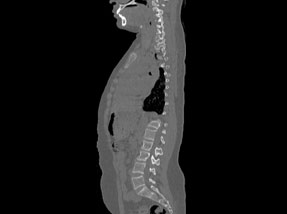

• Pre-SurgeryBefore

• Post SurgeryAfter

Case 1